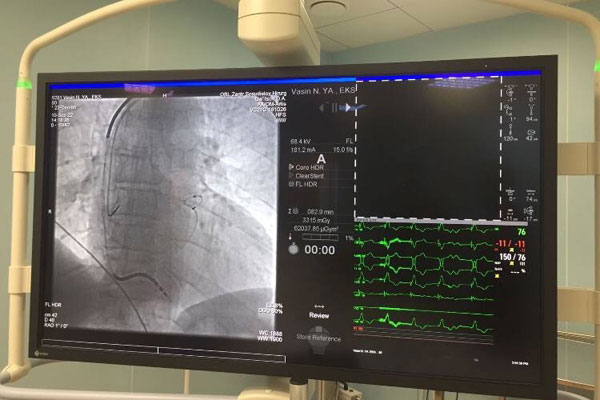

Ассистент кафедры сердечно-сосудистой, рентгенэндоваскулярной хирургии и лучевой диагностики РязГМУ, заведующий отделением Рязанского кардиодипансера, кандидат медицинских наук Владислав Поваров провел вторую операция по установке СРТ-Д.

Первая установка СРТ-Д была проведена осенью прошлого года. Операция прошла успешно. Ранее такие хирургические вмешательства проводились только в федеральных клиниках. Сейчас за счет нацпроекта «Здравоохранение» этот вид высокотехнологичной медпомощи рязанцы получают в Рязанском кардиодиспансере, не выезжая за пределы региона.

«Особенностью данных операций по сравнению с имплантациями других устройств является сильная зависимость их сложности и продолжительности от анатомии пациента. Хирургическое вмешательство было очень непростым. Но положительный результат достигнут: за 2,5 часа, мы, образно говоря, починили «сломанный насос» и приблизили работу сердца пациентки к работе сердца здорового человека», – говорит Владислав Поваров.